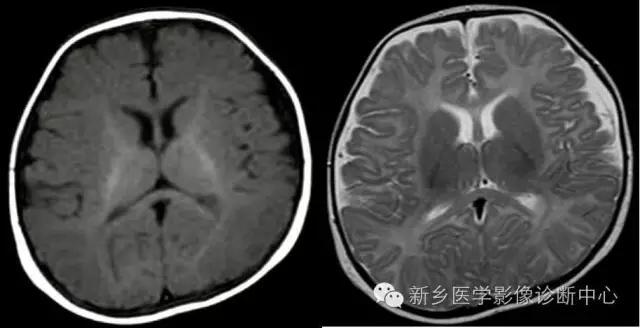

在出生后6个月以内,T1WI是评估髓鞘化进展最有效的序列,与灰质相比,髓鞘化的区域在翻转恢复成像上成高信号;6个月以后绝大多数大脑白质在T1WI上成高信号,超过这段时间在评估髓鞘化过程就要依赖T2WI。到24个月时,除去位于枕顶叶侧脑室旁的终末区,髓鞘化的进程已大部分完成。这些终末区在长TR序列中呈模糊的高信号,这样的改变可以持续至30-40岁。

亦称灰白质信号倒转期。随月龄增长大脑深部白质内水分降低,水分比灰质少,外围区皮质逐渐变薄,白质信号区逐渐扩大。此期中间区(白质)呈低信号,灰质与中央区呈中等信号。